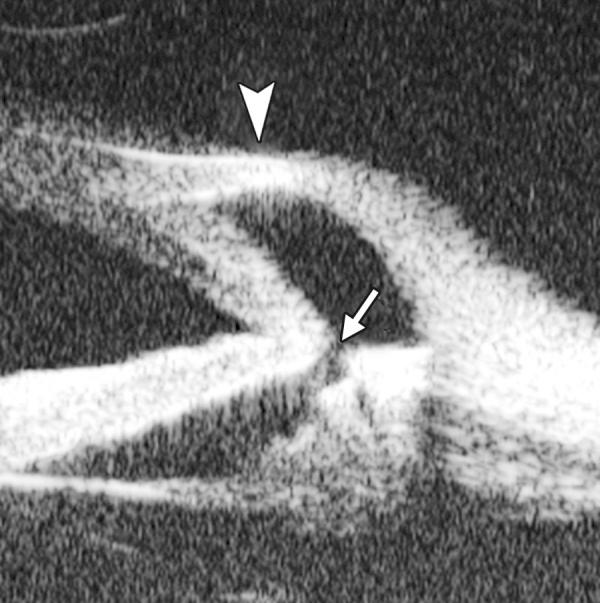

Ultrasound biomicroscopy (UBM) is a high-resolution ultrasound technique that allows noninvasive imaging of structural details of the anterior ocular segment at near light microscopic resolution and provides detailed assessment of anterior segment structures, including those obscured by normal anatomic and pathologic relations. This review gives an overview regarding the instrument, technique and its applications.

超声生物显微镜(UBM)是一种高分辨率超声技术,它能够以接近光学显微镜的分辨率对眼前节结构细节进行无创成像,并对眼前节结构进行详细评估,包括那些被正常解剖和病理关系所掩盖的结构。本文综述了该仪器、技术及其应用。